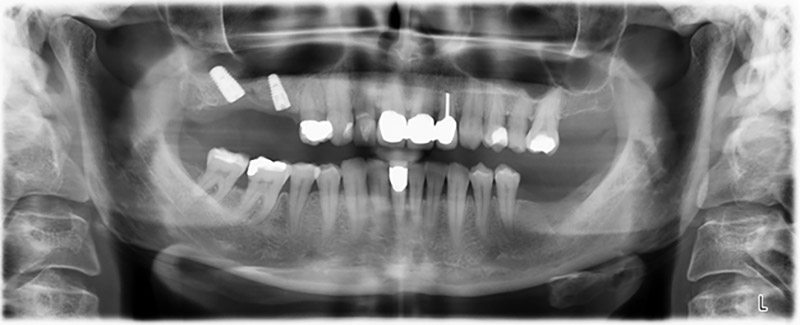

Unos seis meses después de la extracción de las piezas 16 y 14 se realizó una tomografía digital de volúmenes (DVT, Planmeca) para realizar una planificación adecuada y reducir los riesgos al mínimo. En este punto se constató que el hueso no se había regenerado en la cantidad deseada (figuras 2 a 7).

Figuras 2 a 7: Tomografía digital de volúmenes con oferta ósea horizontal reducida.